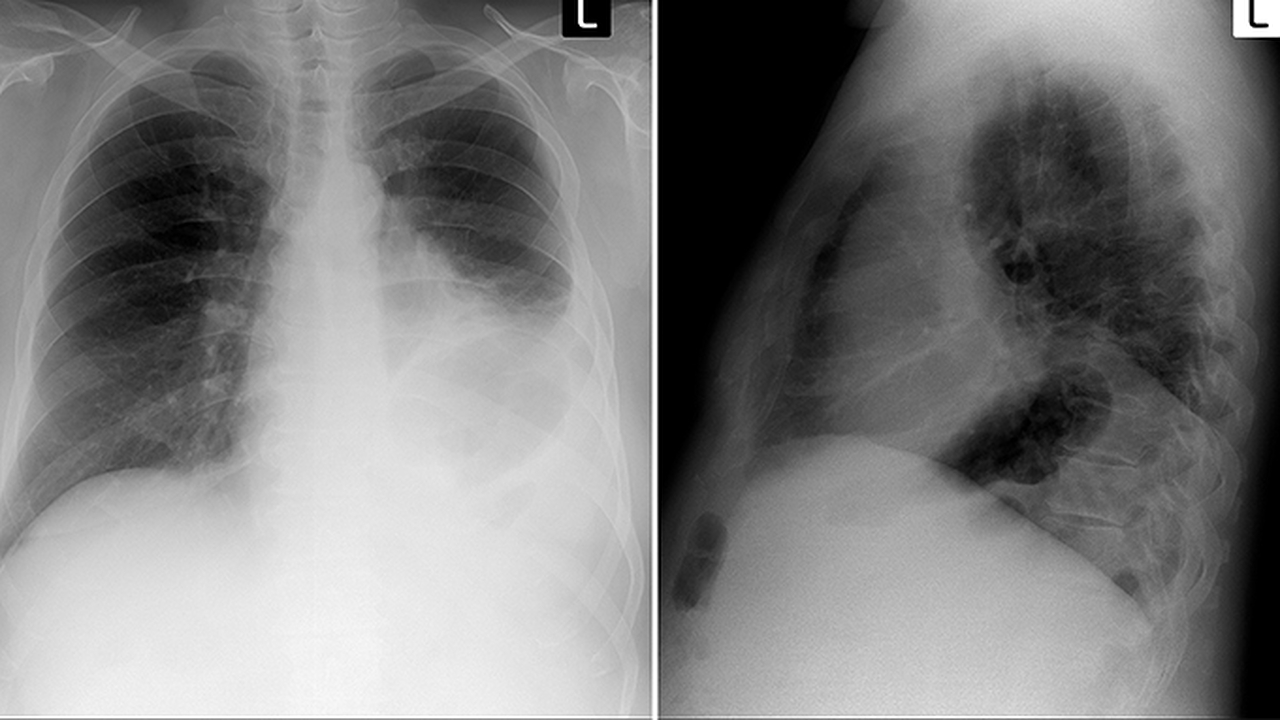

支原體肺炎不一定會發(fā)燒,部分患者可能僅表現為咳嗽、乏力等癥狀。支原體肺炎是由肺炎支原體感染引起的呼吸道疾病,臨床表現存在個體差異。

支原體肺炎患者中,發(fā)熱是常見癥狀之一,但并非所有患者都會出現。典型表現包括持續(xù)性干咳、咽痛、頭痛、肌肉酸痛等,部分患者可能出現低熱或中度發(fā)熱,體溫多在37.5-38.5攝氏度之間。兒童患者發(fā)熱概率相對較高,成人可能僅表現為輕微不適。癥狀嚴重程度與感染者免疫狀態(tài)、年齡等因素相關。